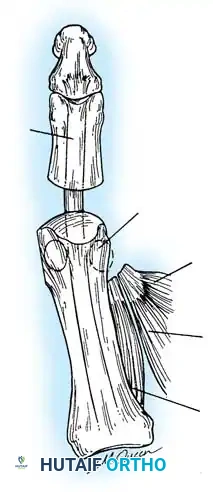

Fig. 78-31 Excision of fi bular sesamoid in modifi ed Keller procedure. With base of proximal phalanx removed and medial eminence excision, exposure of fi bular sesamoid is not as diffi cult from medial incision. A, Operative photograph showing elevation of fi rst metatarsal with strong two-tooth retractor and use of small osteotome to mobilize fi bular sesamoid and lateral capsuloligamentous (frequently contracted) structures. Osteotome is between metatarsal head and lateral sesamoid. When mobilization of fi bular sesamoid is complete, entire sesamoid is visible for excision. Note chondromalacia of tibial sesamoid articular surface medial to osteotome. B, Fibular sesamoid has been excised, and lateral capsular structures and conjoined tendon (in forceps) have been released. Neurovascular bundle to lateral side of hallux is adjacent to these structures. C, Diagrammatic representation of modifi ed Keller procedure. By excising fi bular sesamoid, valgus moment of conjoined tendon of fl exor hallucis brevis and adductor hallucis no longer pulls fl exor hallucis longus tendon laterally (carrying hallux with it) through capsulosesamoid plantar plate and pulley system. D, Metatarsal head must be lifted dorsally to excise fi bular sesamoid under direct vision. E, Note exposure of fi bular sesamoid after mobilization of metatarsal head. Continued